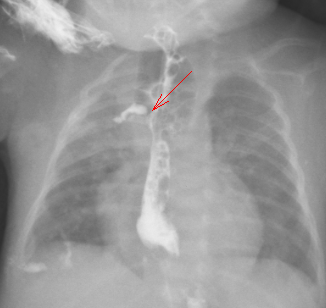

图 1:术前造影片

患者女,4 小时 51 分钟,入院情况:患儿系 4 胎 0 产,胎龄 31+5 周,单胎,因「重度先兆子痫、产前脐血流 S/D 比值高」剖宫产娩出, 有宫内窘迫(具体不详),无胎膜早破。无羊水污染,胎盘正常。Apgar 评分 1 分钟 9 分,5 分钟 9 分,10 分钟 9 分,出生体重 1500 g。出生后无窒息抢救史,4 小时前因「早产儿」在当地医院新生儿科住院,下胃管时受阻考虑食管闭锁,与家属沟通后家属要求转院治疗,遂由我科医护人员转运至我院。急诊以「食道闭锁、早产儿」收住入院。病程中患儿自发病以来,神志清,精神反应欠佳,未开奶,无呕吐、腹胀等症状,胎便已排,小便不详。心脏检查 (常规, 左心功能测定, 室壁运动分析) 彩超检查提示:先天性心脏病:室间隔缺损(肌部);房间隔缺损(中央型);彩色多普勒显示: 室水平左向右分流;房水平左向右分流。2021-08-18 日行胸部 (正位), 腹部 (正位)CR 检查示:先天性食道闭锁;新生儿肺炎较前加重,右肺上叶肺不张;肠管充气减少。上消化道造影 (数字化摄影) 检查示:1. 食道闭锁;2. 新生儿肺炎。不能喂养,有手术指征,完善术前检查,加强呼吸道管理,限期手术。积极完善术前检查,于 2021-08-19 急诊行右后外侧入路经胸膜外食管探查、食管气管瘘修补、食管吻合术。

2021-08-17 10:01 降钙素原:0.34 ng/ml。心电图:窦性心动过缓,电轴不偏,异常心电图:Q-T 间期延长,注意动态随访。胸部 (正位)CR 检查示:先天性食道闭锁不除外;新生儿肺炎;肠管充气减少。